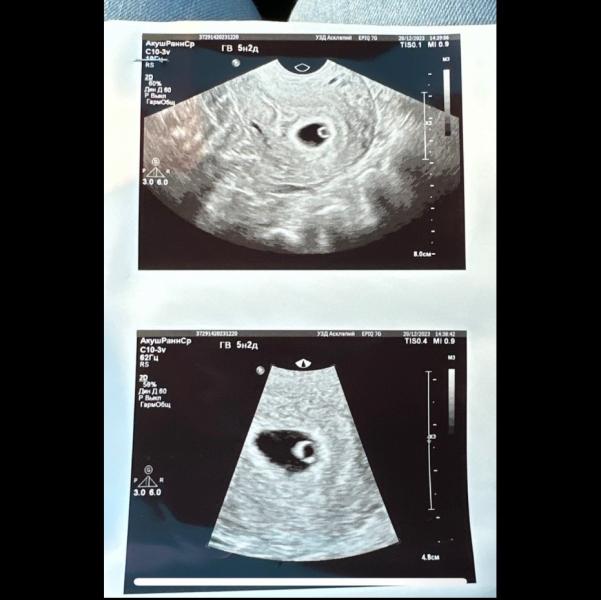

Ура! Пульсация есть, 5-6 недель! Когда ждать первое УЗИ и сердцебиение? Срок

Вот она, моя крошечка🥹

Эмбрион четко не увидели, но пульсация уже есть, по плодному яйцу 5 недель 6 дней. Теперь 30 декабря запишусь сердечко слушать! 🥰